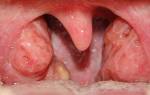

Как выглядит рак щеки? Первым признаком, свидетельствующим о появлении онкологии, считается небольшая шишка, выпирающая через слизистый эпителий щёчной области, которую легко можно ощутить языком. Со временем она не исчезает, а покрывается трещинами и белёсым налётом.

- Узловая. Эта форма злокачественного новообразования возвышается над эпителием щёчной области и выглядит как уплотнение, имеющее чёткие формы. Поверхность слизистого слоя над поражённым участком или остаётся неизменной, или на ней появляются светлые пятна.

- Паппилярная. Рак щеки такой формы напоминает кочан цветной капусты. Плотные, ороговевшие наросты свисают к зубам и мешают пережёвывать пищу. Данная разновидность онкопоражения считается самой благоприятной, поскольку аномальный процесс не выходит за пределы капсулы, покрывающей опухоль.

Как выглядит начальная стадия рака ротовой полости? На начальной стадии проявления заболевания достаточно безболезненны. Можно заметить красные или белые пятна на слизистой, язвочки, трещины, узелки. Видоизмененные участки могут быть безболезненными и никак не беспокоить, или же могут кровоточить.